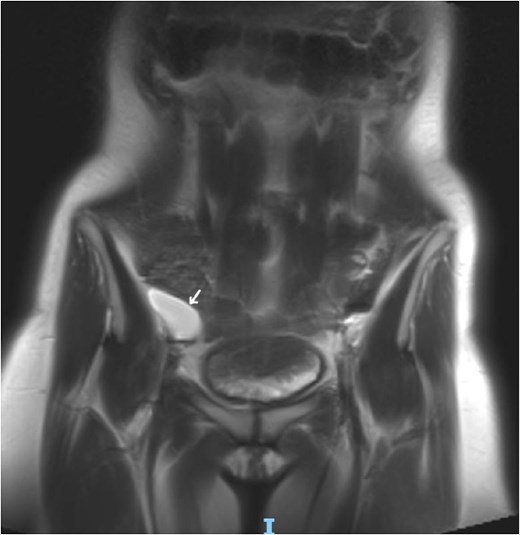

Laboratory studies, including complete blood count and comprehensive metabolic panel, were within normal limits. Initial ultrasonography (US) revealed an oblong cystic lesion with fine septations, measuring 6.5 × 3 cm, extending through the right inguinal canal into the labium majus (Figs 1 and 2). Subsequent pelvic magnetic resonance imaging (MRI) corroborated these findings, demonstrating a right lower abdominal cystic lesion with thin septations extending to the inguinal region, showing low T1 and high T2 signal intensity, measuring ~7 × 3.5 cm (Figs 3 and 4). No evidence of bowel or omental herniation was observed, suggesting canal of Nuck hydrocele.

Coronal MRI view of the pelvis, showing well-defined cystic lesion with low T1 and high T2 signal intensity, measuring ~ 7 × 3.5 cm (arrow).